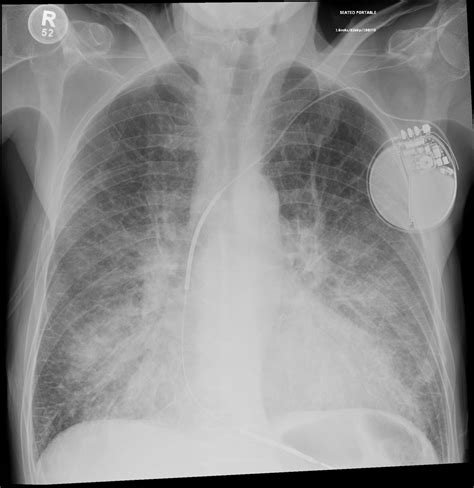

Okay, let’s get to the nitty-gritty. How do you actually spot these pulmonary segments on a chest X-ray? It’s like reading a map, but instead of streets and landmarks, you’re looking for subtle differences in density and shadows. First off, remember that a standard chest X-ray is a two-dimensional image of a three-dimensional structure, which means things can overlap and appear distorted. But don’t worry, with a bit of practice and some key anatomical knowledge, you’ll get the hang of it.

Start by identifying the major landmarks: the trachea, heart, diaphragm, and ribs. Then, focus on the lung fields themselves. Look for any areas of increased density (appearing whiter) or decreased density (appearing darker). These could indicate abnormalities within the segments. For example, a consolidation in the right upper lung field might suggest pneumonia in the apical or posterior segment of the right upper lobe. You’ll also need to mentally superimpose the anatomical map of the pulmonary segments onto the X-ray image. This takes practice, but there are plenty of resources available, including diagrams and online tutorials, that can help. Additionally, pay attention to the angles of the X-ray. A PA (posterior-anterior) view is standard, but sometimes a lateral view is also taken, which can provide a different perspective and help you better localize abnormalities. Remember, identifying pulmonary segments on a chest X-ray isn’t about memorizing exact locations; it’s about understanding the underlying anatomy and recognizing patterns of disease. With patience and persistence, you’ll become a pro at spotting those segments in no time.